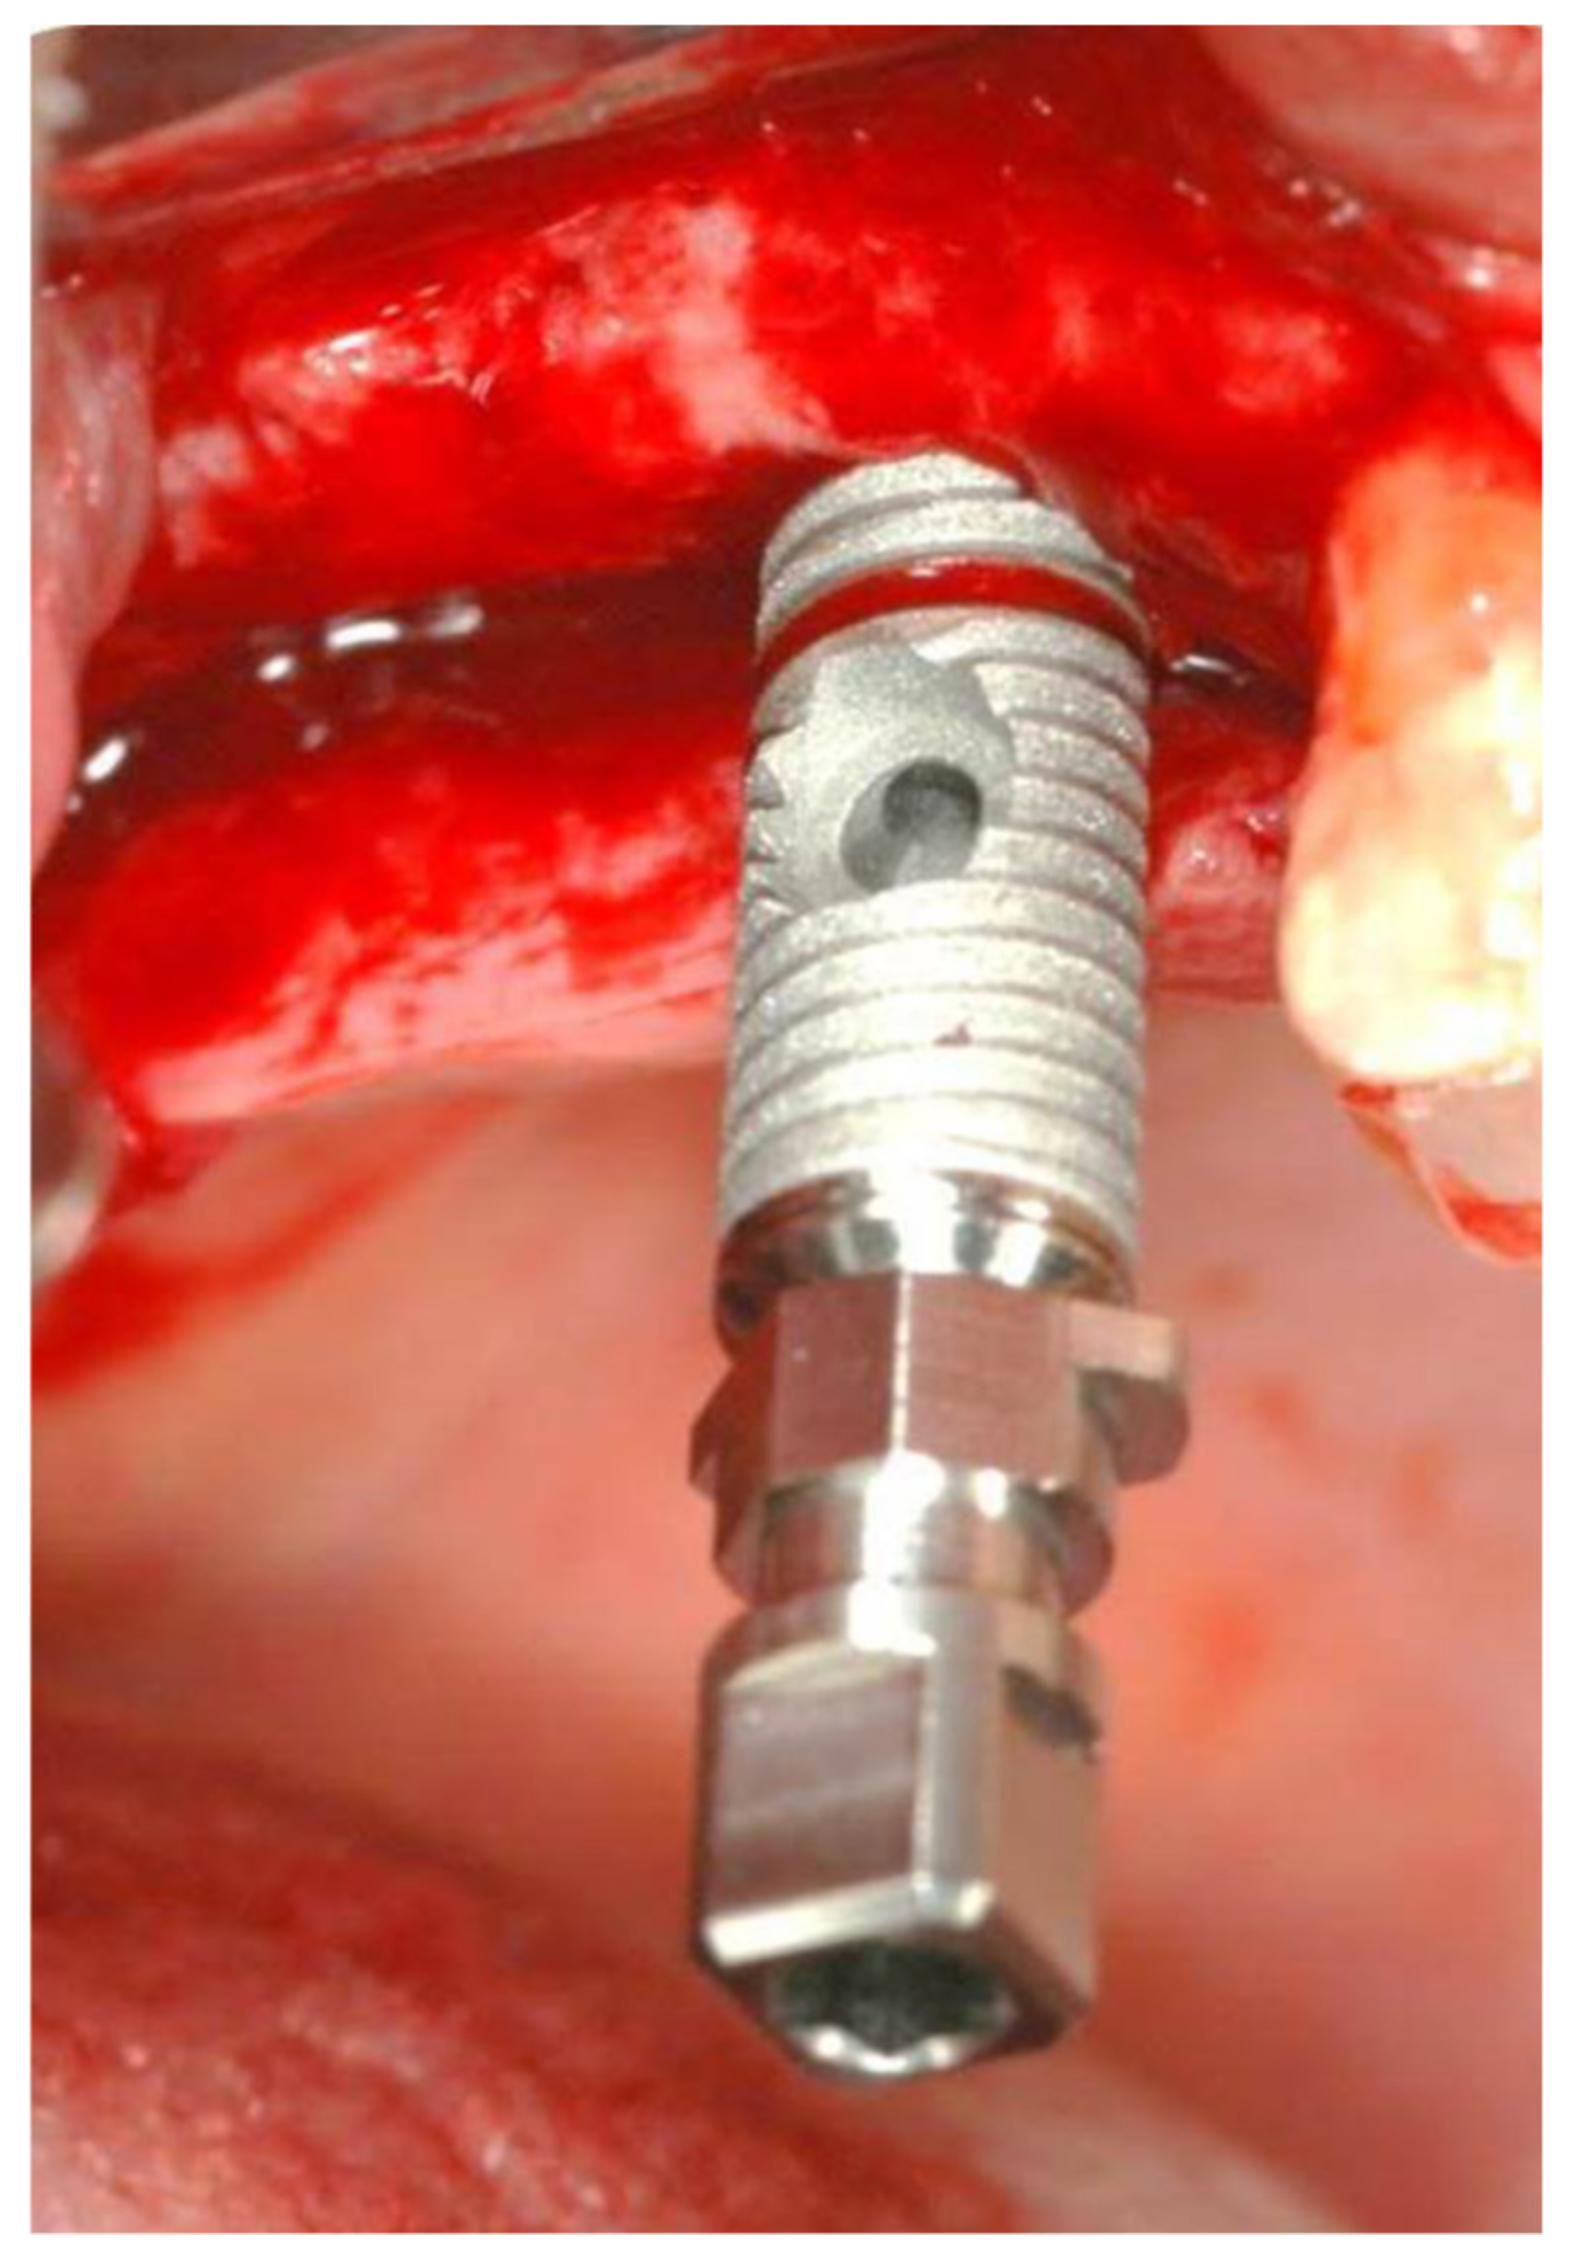

2. Materials and Methods

2.1. Standard Surgical Procedure